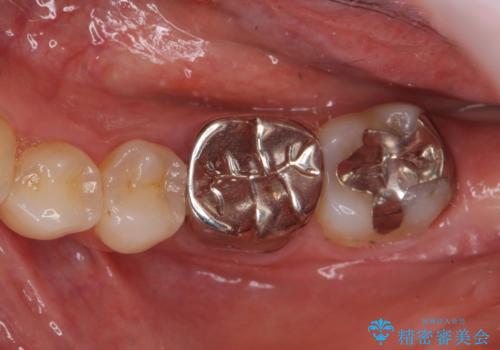

[フルジルコニアクラウン] 老朽化した銀歯を白く

![[フルジルコニアクラウン] 老朽化した銀歯を白くの症例 治療前](https://seimitsushinbi.jp/wp/wp-content/uploads/2020/05/095ef1aef9dfbbc03d4a7b2f7a38a13c-500x350.jpg?v=1588518714)